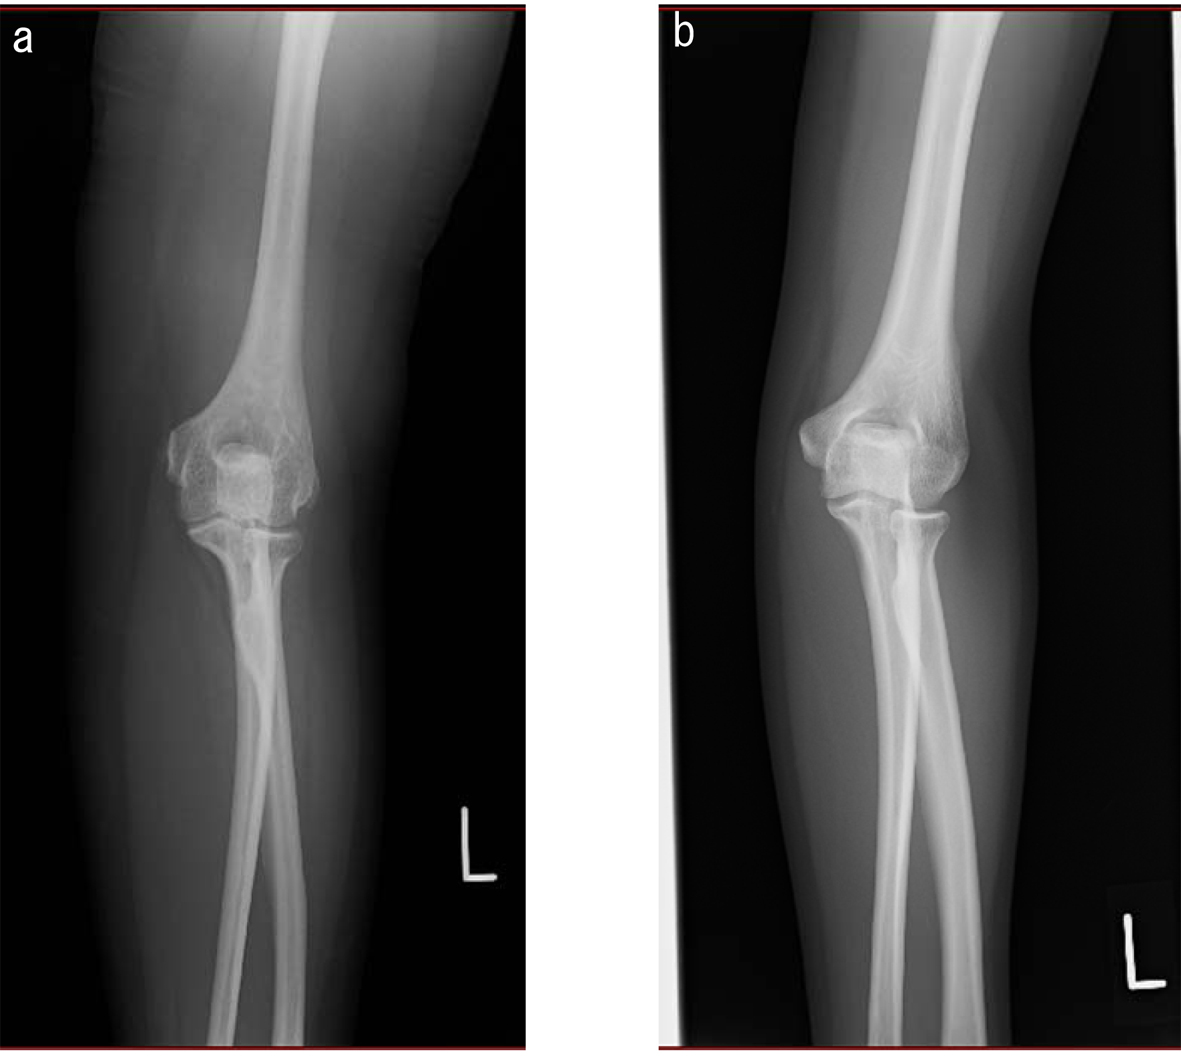

A 46-year-old woman was admitted for the treatment of type 2 diabetes. She was diagnosed as having type 2 diabetes 2 years ago. She had mental retardation and epileptic seizure in early childhood. Her gait was unstable until she became 6 years old. Her father, paternal grandmother and aunt also had mental retardation. Her body height, weight, body mass index and abdominal circumference were 149.5 cm, 76.2 kg, 34.2 kg/m2 and 92 cm, respectively. She showed round face, short stature, central obesity and short fingers and toes, suggesting the existence of AHO. She also has pleasant nature, supporting the diagnosis of AHO. Surprisingly, her bones of extremities were very thin (Fig. 1), with normal bone density. Normal serum levels of calcium, inorganic phosphorus and intact parathyroid hormone (PTH), and a negativity of the Ellsworth-Howard test suggested the existence of PPHP. Interestingly, ossification of entheses was also observed (Fig. 2). DNA sequence analysis showed a novel mutation in exon 1 (c.137 T > G, L46P) of the GNAS gene (Fig. 3). She was heterozygous for this mutation.

![]() Click for large image | Figure 1. Radiograph of arm in a patient with pseudopseudohypoparathyroidism. Arm of (a) a patient and (b) a 35-year-old normal woman with body height 154 cm, body weight 46 kg and body mass index 19.4 kg/m2. |